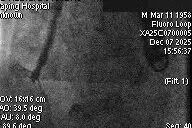

After general anesthesia, the patient underwent jugular vein puncture to establish access. An 18Fr delivery sheath was advanced over a super-stiff guidewire to the mid-to-lower right atrium. Under ultrasound guidance, the delivery system was introduced. A 14T K-Clip® and a 16T K-Clip® device were implanted at the postero-septal commissure annulus and the antero-posterior commissure annulus, respectively. The angle between the device and the annular plane was adjusted through controlled flexion and rotation to orient the device tip toward the target site. Using ultrasound MPR mode, the anchor component was advanced into the annulus. After traction confirmed stability, the clip arms were opened and apposed to the annulus. The anchor component was then retracted to close the clip arms, achieving annuloplasty. The effect was evaluated as satisfactory, and the clip components were deployed.

Second clip placed at postero-septal commissure using the same steps

Both clips stable